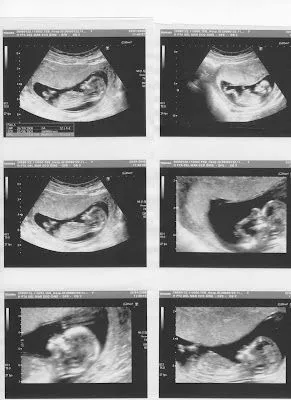

Diario de un embarazo > Diario de un embarazo

Indica el motivo para eliminar esta imagen: